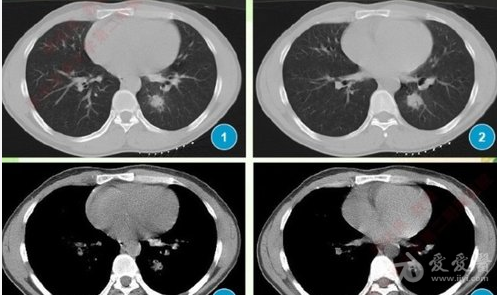

多发小结节状卫星灶的肺结核

存在气道播散,表现为肺癌主病灶旁小灶高密度影,类似结核球周边的卫星

体检发现右肺肿块,周围有多发粟粒状,小斑片状影,提示结核球伴卫星灶